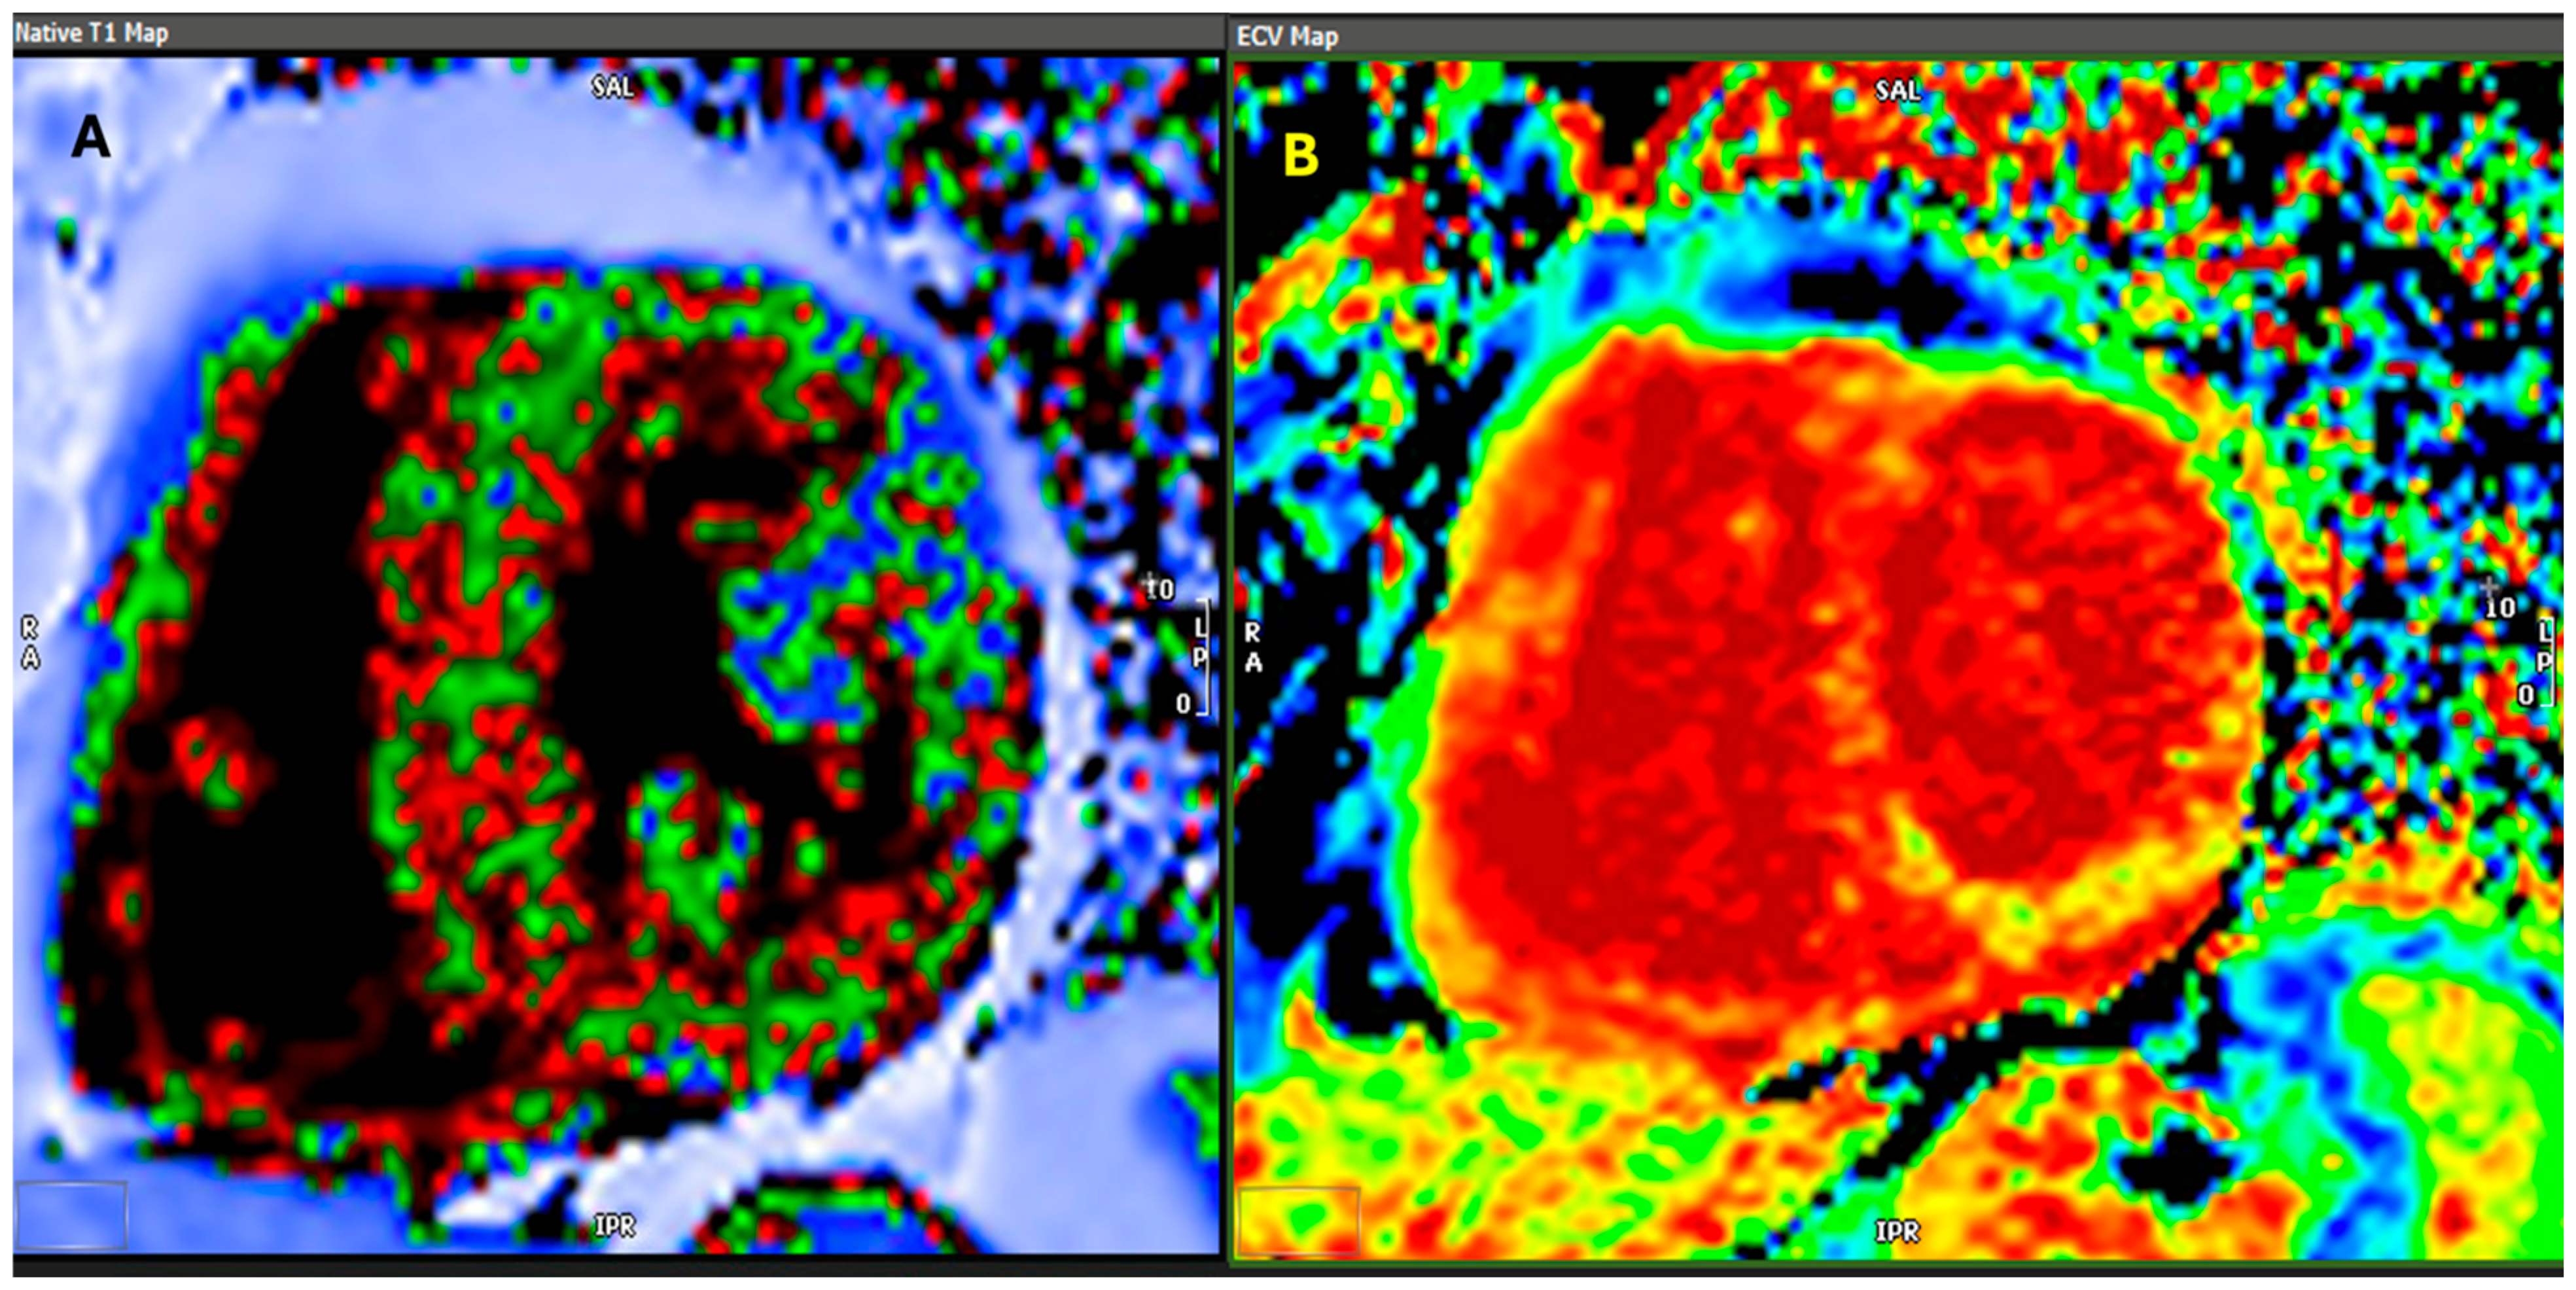

- Banypersad, S.M.; Sado, D.M.; Flett, A.S.; Gibbs, S.D.; Pinney, J.H.; Maestrini, V.; Cox, A.T.; Fontana, M.; Whelan, C.J.; Wechalekar, A.D.; et al. Quantification of myocardial extracellular volume fraction in systemic AL amyloidosis: An equilibrium contrast cardiovascular magnetic resonance study. Circ. Cardiovasc. Imaging 2013, 6, 34–39. [Google Scholar] [CrossRef] [PubMed]

- Messroghli, D.R.; Moon, J.C.; Ferreira, V.M.; Grosse-Wortmann, L.; He, T.; Kellman, P.; Mascherbauer, J.; Nezafat, R.; Salerno, M.; Schelbert, E.B.; et al. Clinical recommendations for cardiovascular magnetic resonance mapping of T1, T2, T2* and extracellular volume: A consensus statement by the Society for Cardiovascular Magnetic Resonance (SCMR) endorsed by the European Association for Cardiovascular Imaging (EACVI). J. Cardiovasc. Magn. Reson. 2017, 19, 75, Erratum in J. Cardiovasc. Magn. Reson. 2018, 20, 9. [Google Scholar]

- Fontana, M.; Chung, R.; Hawkins, P.N.; Moon, J.C. Cardiovascular magnetic resonance for amyloidosis. Heart Fail. Rev. 2015, 20, 133–144. [Google Scholar] [CrossRef]